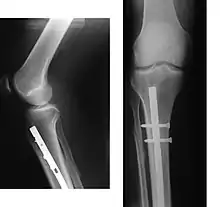

Internal and external views of an arm with a compound fracture, both before and after surgery | |